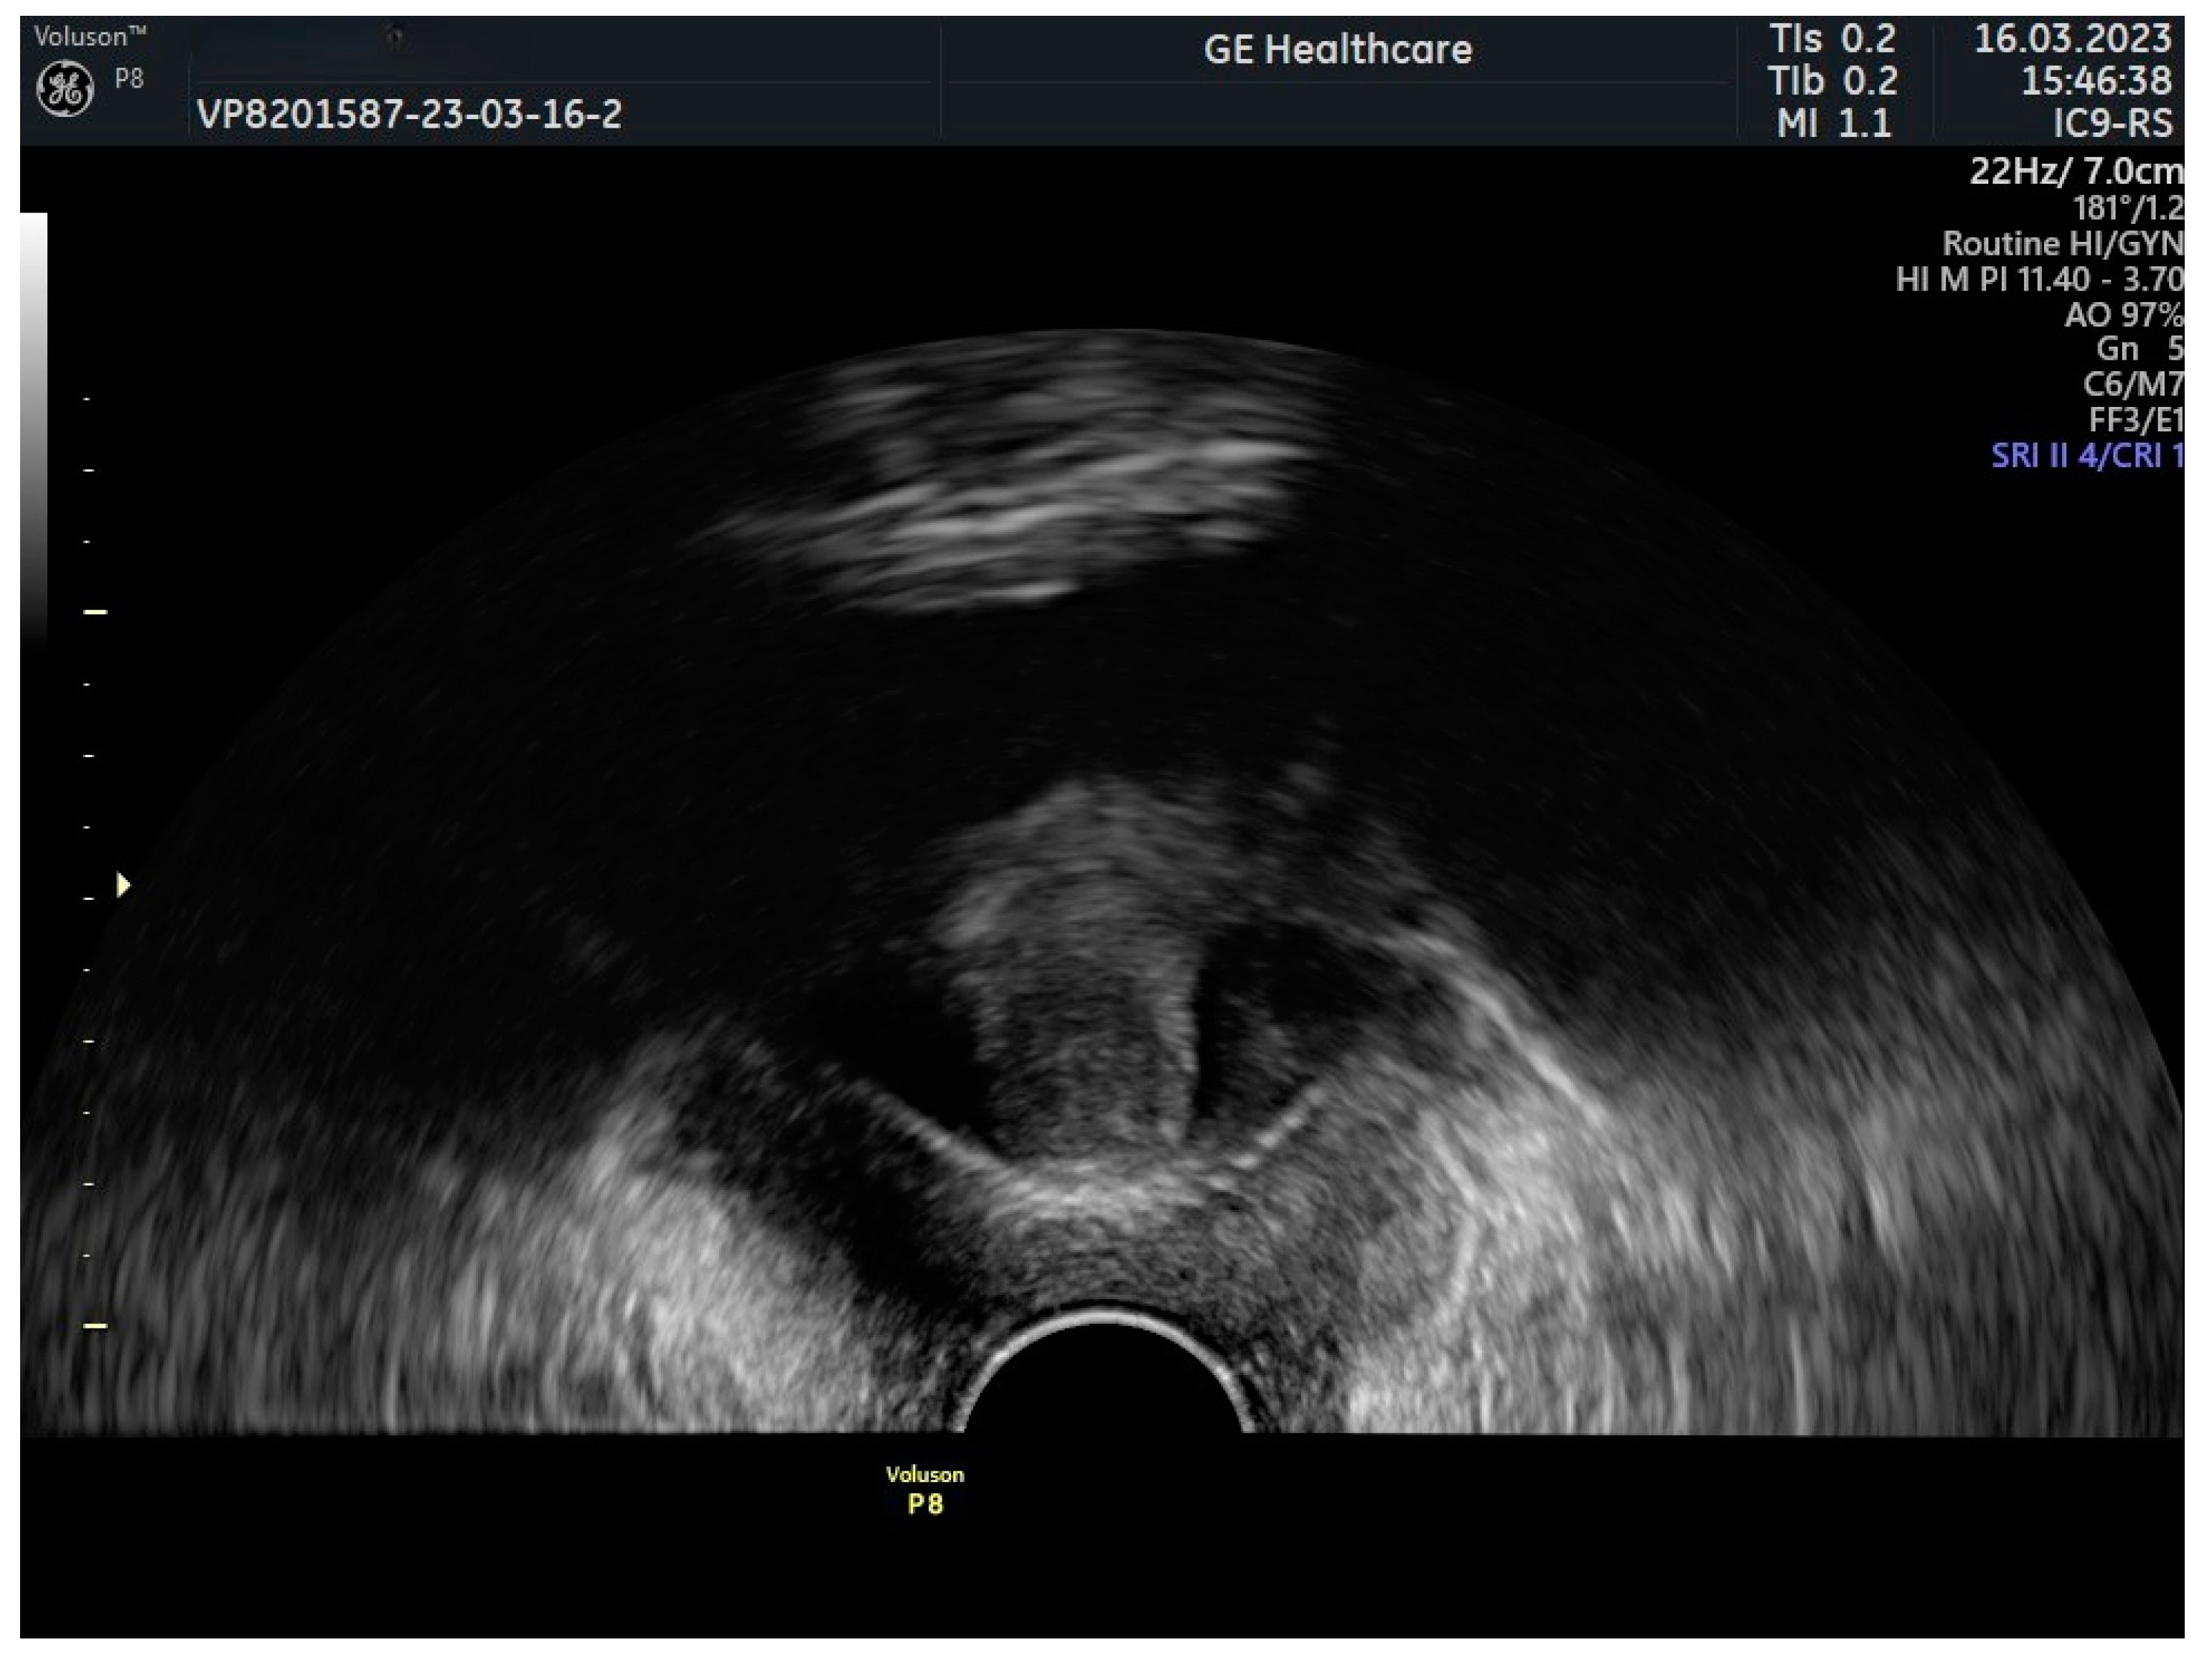

- transvaginal and transrectal approaches;

- external methods: perineal, introital, and transabdominal approaches [14].